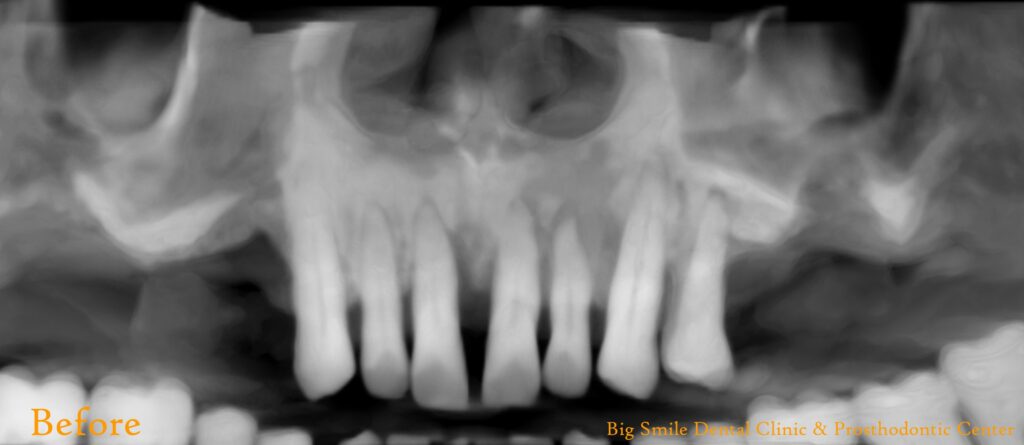

A 50-year-old male patient from New Zealand arrived at our clinic seeking to replace his upper teeth. He had recently returned to Nepal for a 20-day visit and had already explored treatment options at other dental facilities. Unsatisfied with both the proposed treatment plans and the costs, he came to us with his desires and expectations. We listened attentively, taking careful note of his needs. He had already had X-rays taken at the request of a previous dentist.

On his first visit, we performed a thorough examination of his teeth and gums. He had upper back teeth missing and remaining upper front teeth were mobile, whereas his lower teeth were not mobile but required gums treatment. We explained his condition of oral hygiene and treatment required. We presented him with all available options, including removable and fixed prostheses. He opted for a fixed prosthesis with upper arch replacement using 4 dental implants (All-on-4). We also discussed different implant brands and types, and he selected Bredent Copasky implants (Fast & Fixed). Additionally, we offered various prosthetic options for permanent prosthesis, and he chose a hybrid denture.

Fig: Pre-operative extra-oral, intra-oral photographs and X-ray